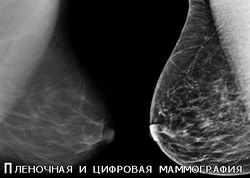

Маммография молочной железы – это вид исследования молочных желез при помощи рентгеновского излучения низких доз. Эта процедура является наиболее распространенным методом для диагностирования рака груди.

На снимках, полученных при помощи маммографа, можно рассмотреть доброкачественные и злокачественные образования. Этим и ценна маммография. Так, например, можно обнаружить наличие кальцинатов – сосредоточения солей кальция. Если они скапливаются в небольшие, но многочисленные образования, то это может свидетельствовать о развитии рака, так как характерны для гиперактивности клеток.

Если же кальцинаты имеют большие размеры, то их наличие не является поводом заподозрить злокачественные образования.